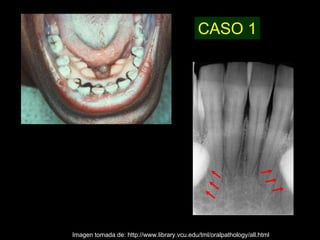

CASO 1

Imagen tomada de: http://www.library.vcu.edu/tml/oralpathology/all.html